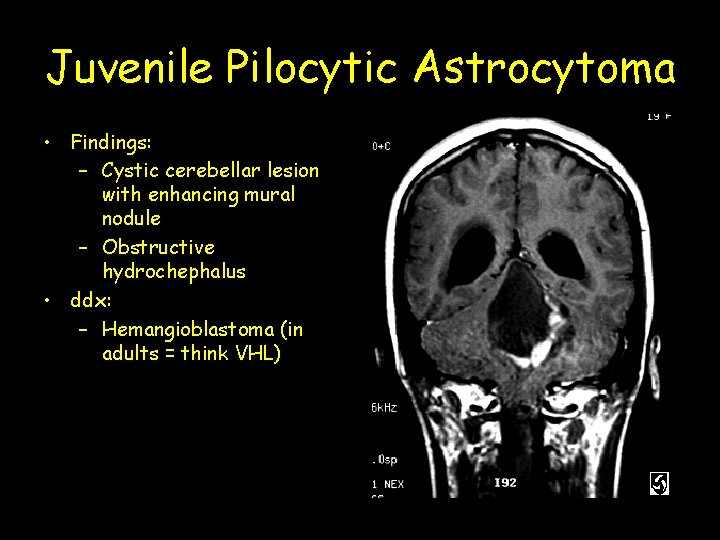

Juvenile Pilocytic Astrocytoma • Findings: – Cystic cerebellar lesion with enhancing mural nodule – Obstructive hydrochephalus • ddx: – Hemangioblastoma (in adults = think VHL)